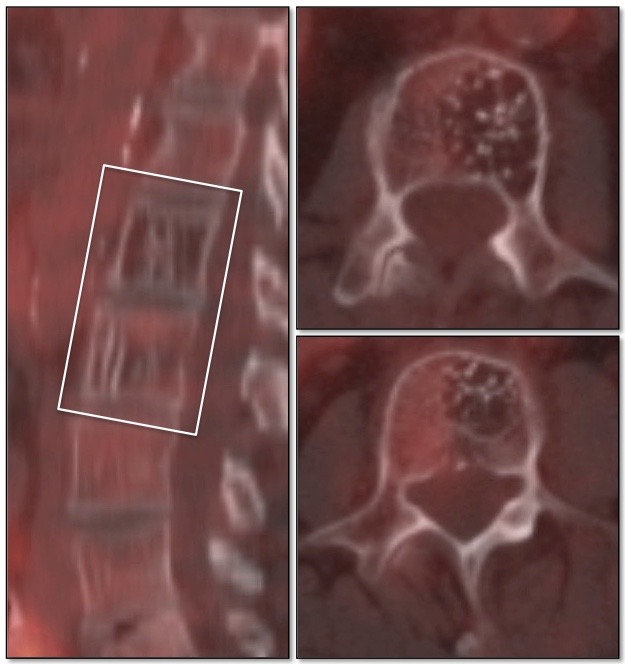

Vertebral Body Hemangioma:

Vertebral body hemangiomas are regularly seen on PET/CT scans and are non-avid.

On CT images, they classically demonstrate a “striated” appearance on sagittal images and a “stippled” appearance on axial images.

While the CT appearance alone is usually diagnostic for hemangiomas, there are cases when it is reassuring to confirm the diagnosis by an absence of metabolic activity on the PET portion of the exam (particularly for those cases where a prior MRI has been equivocal, suggesting the possibility of an “atypical hemangioma”).